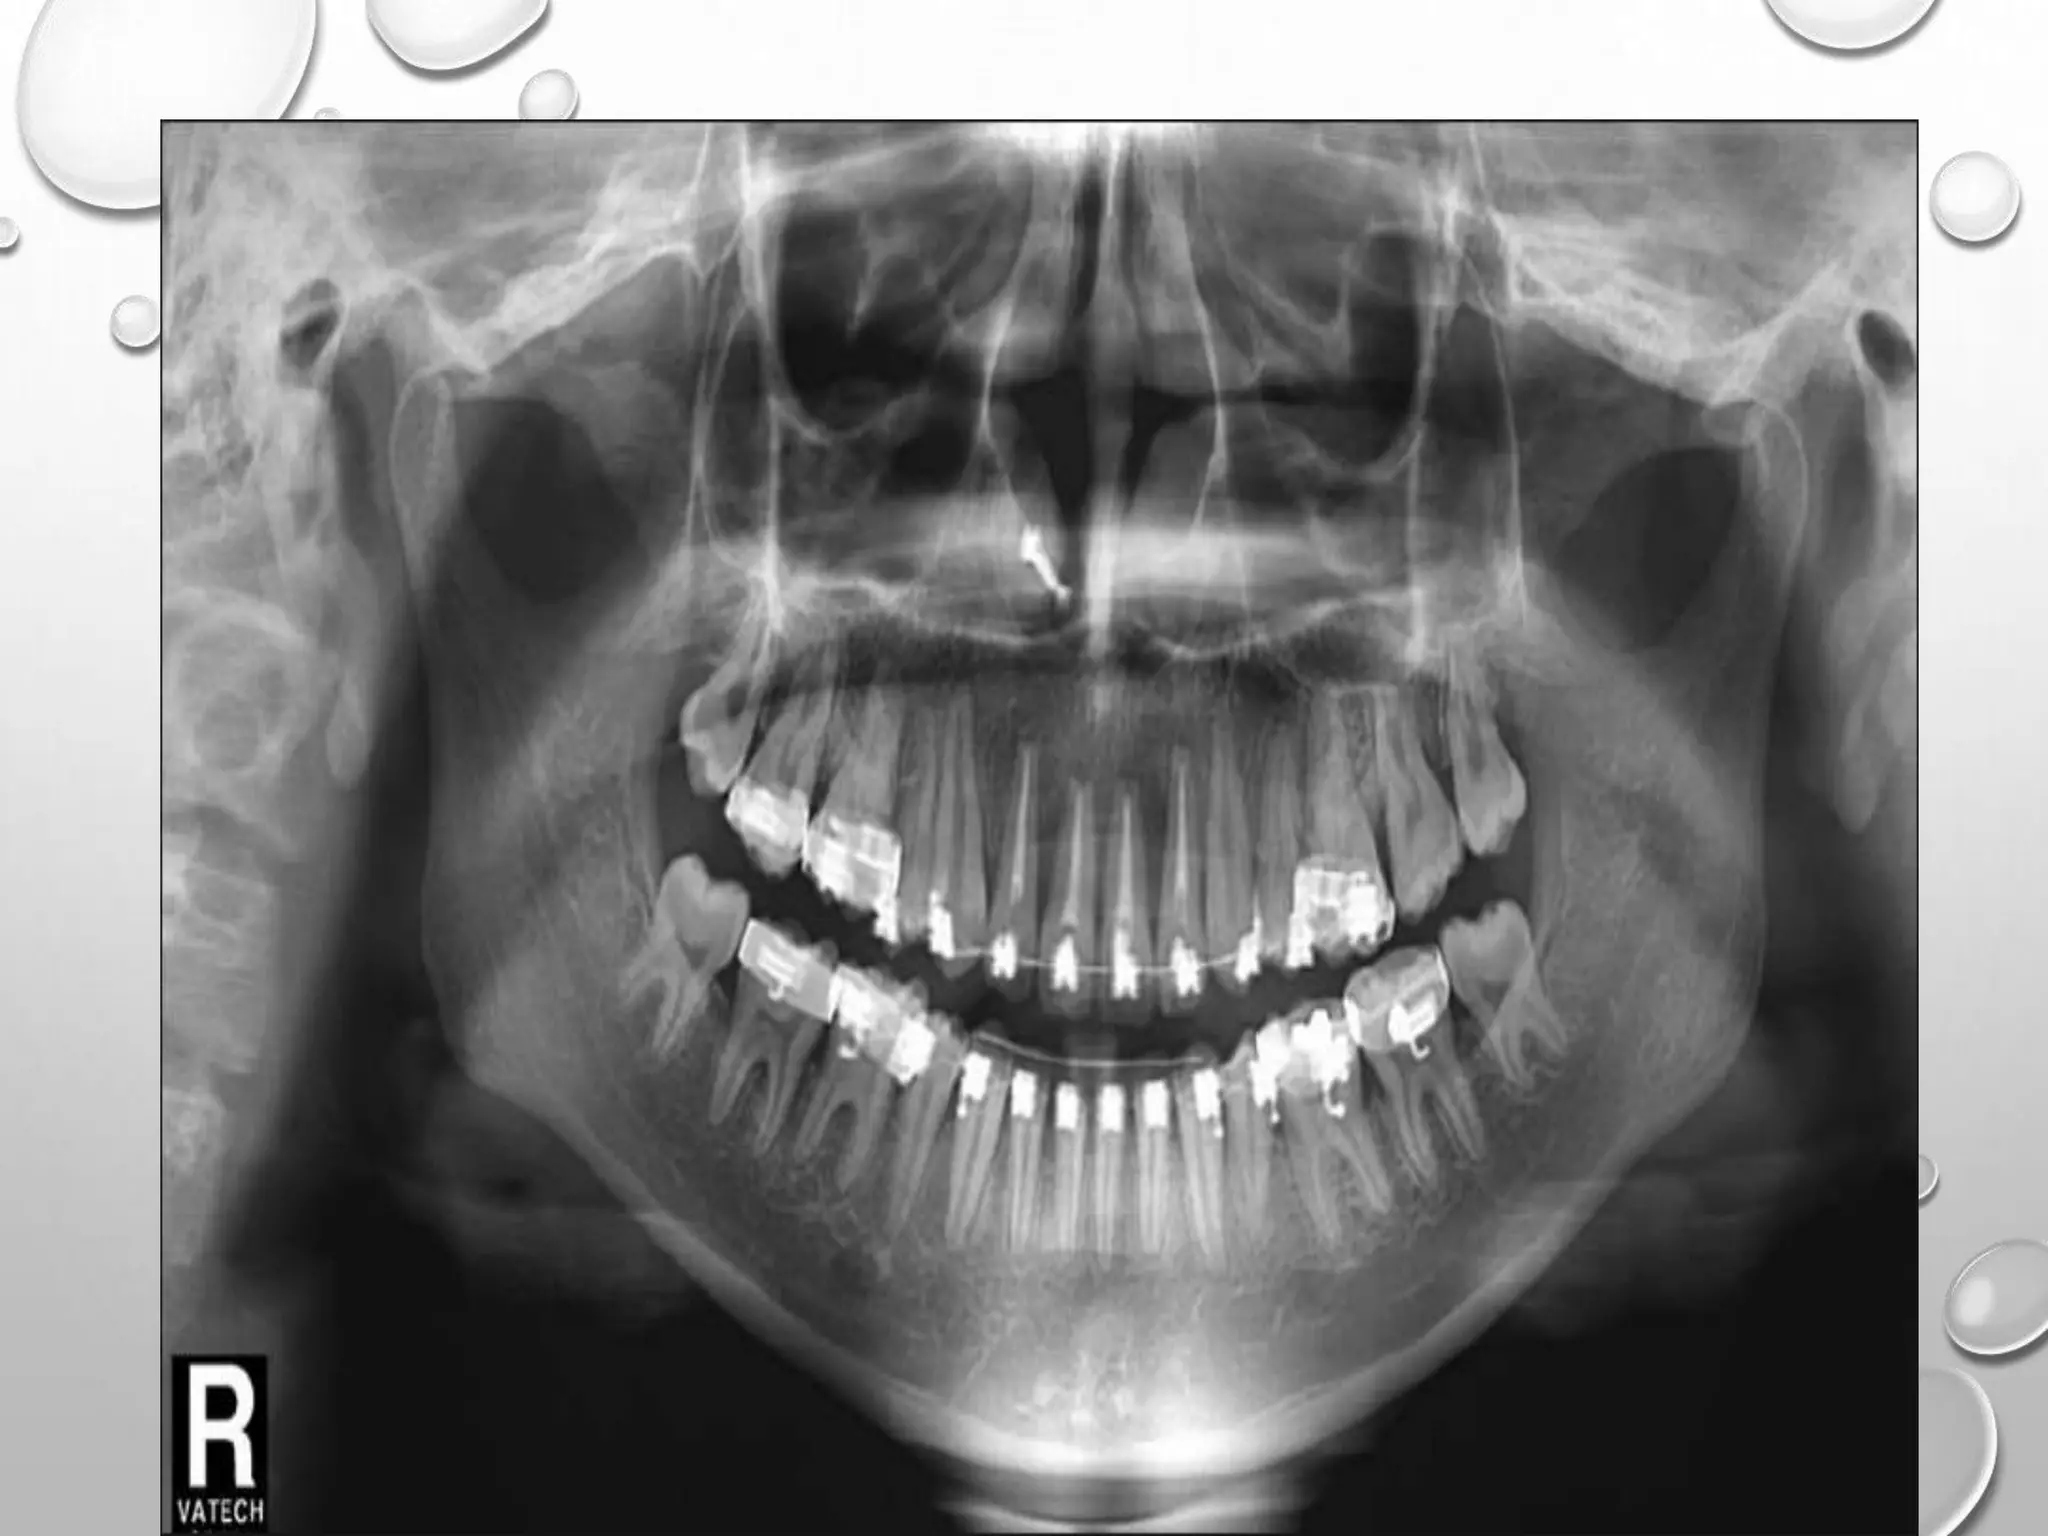

SERIAL PANORAMIC RADIOGRAPHS CONFIRMED THE

UPRIGHTING OF THE MANDIBULAR PREMOLARS AND

FIRST MOLARS, AND FAVORABLE ROOT PARALLELISM.

MESIAL DRIFTING OF THE MANDIBULAR THIRD

MOLARS AND A GOOD ERUPTION PATH OF UPPER

THIRD MOLARS